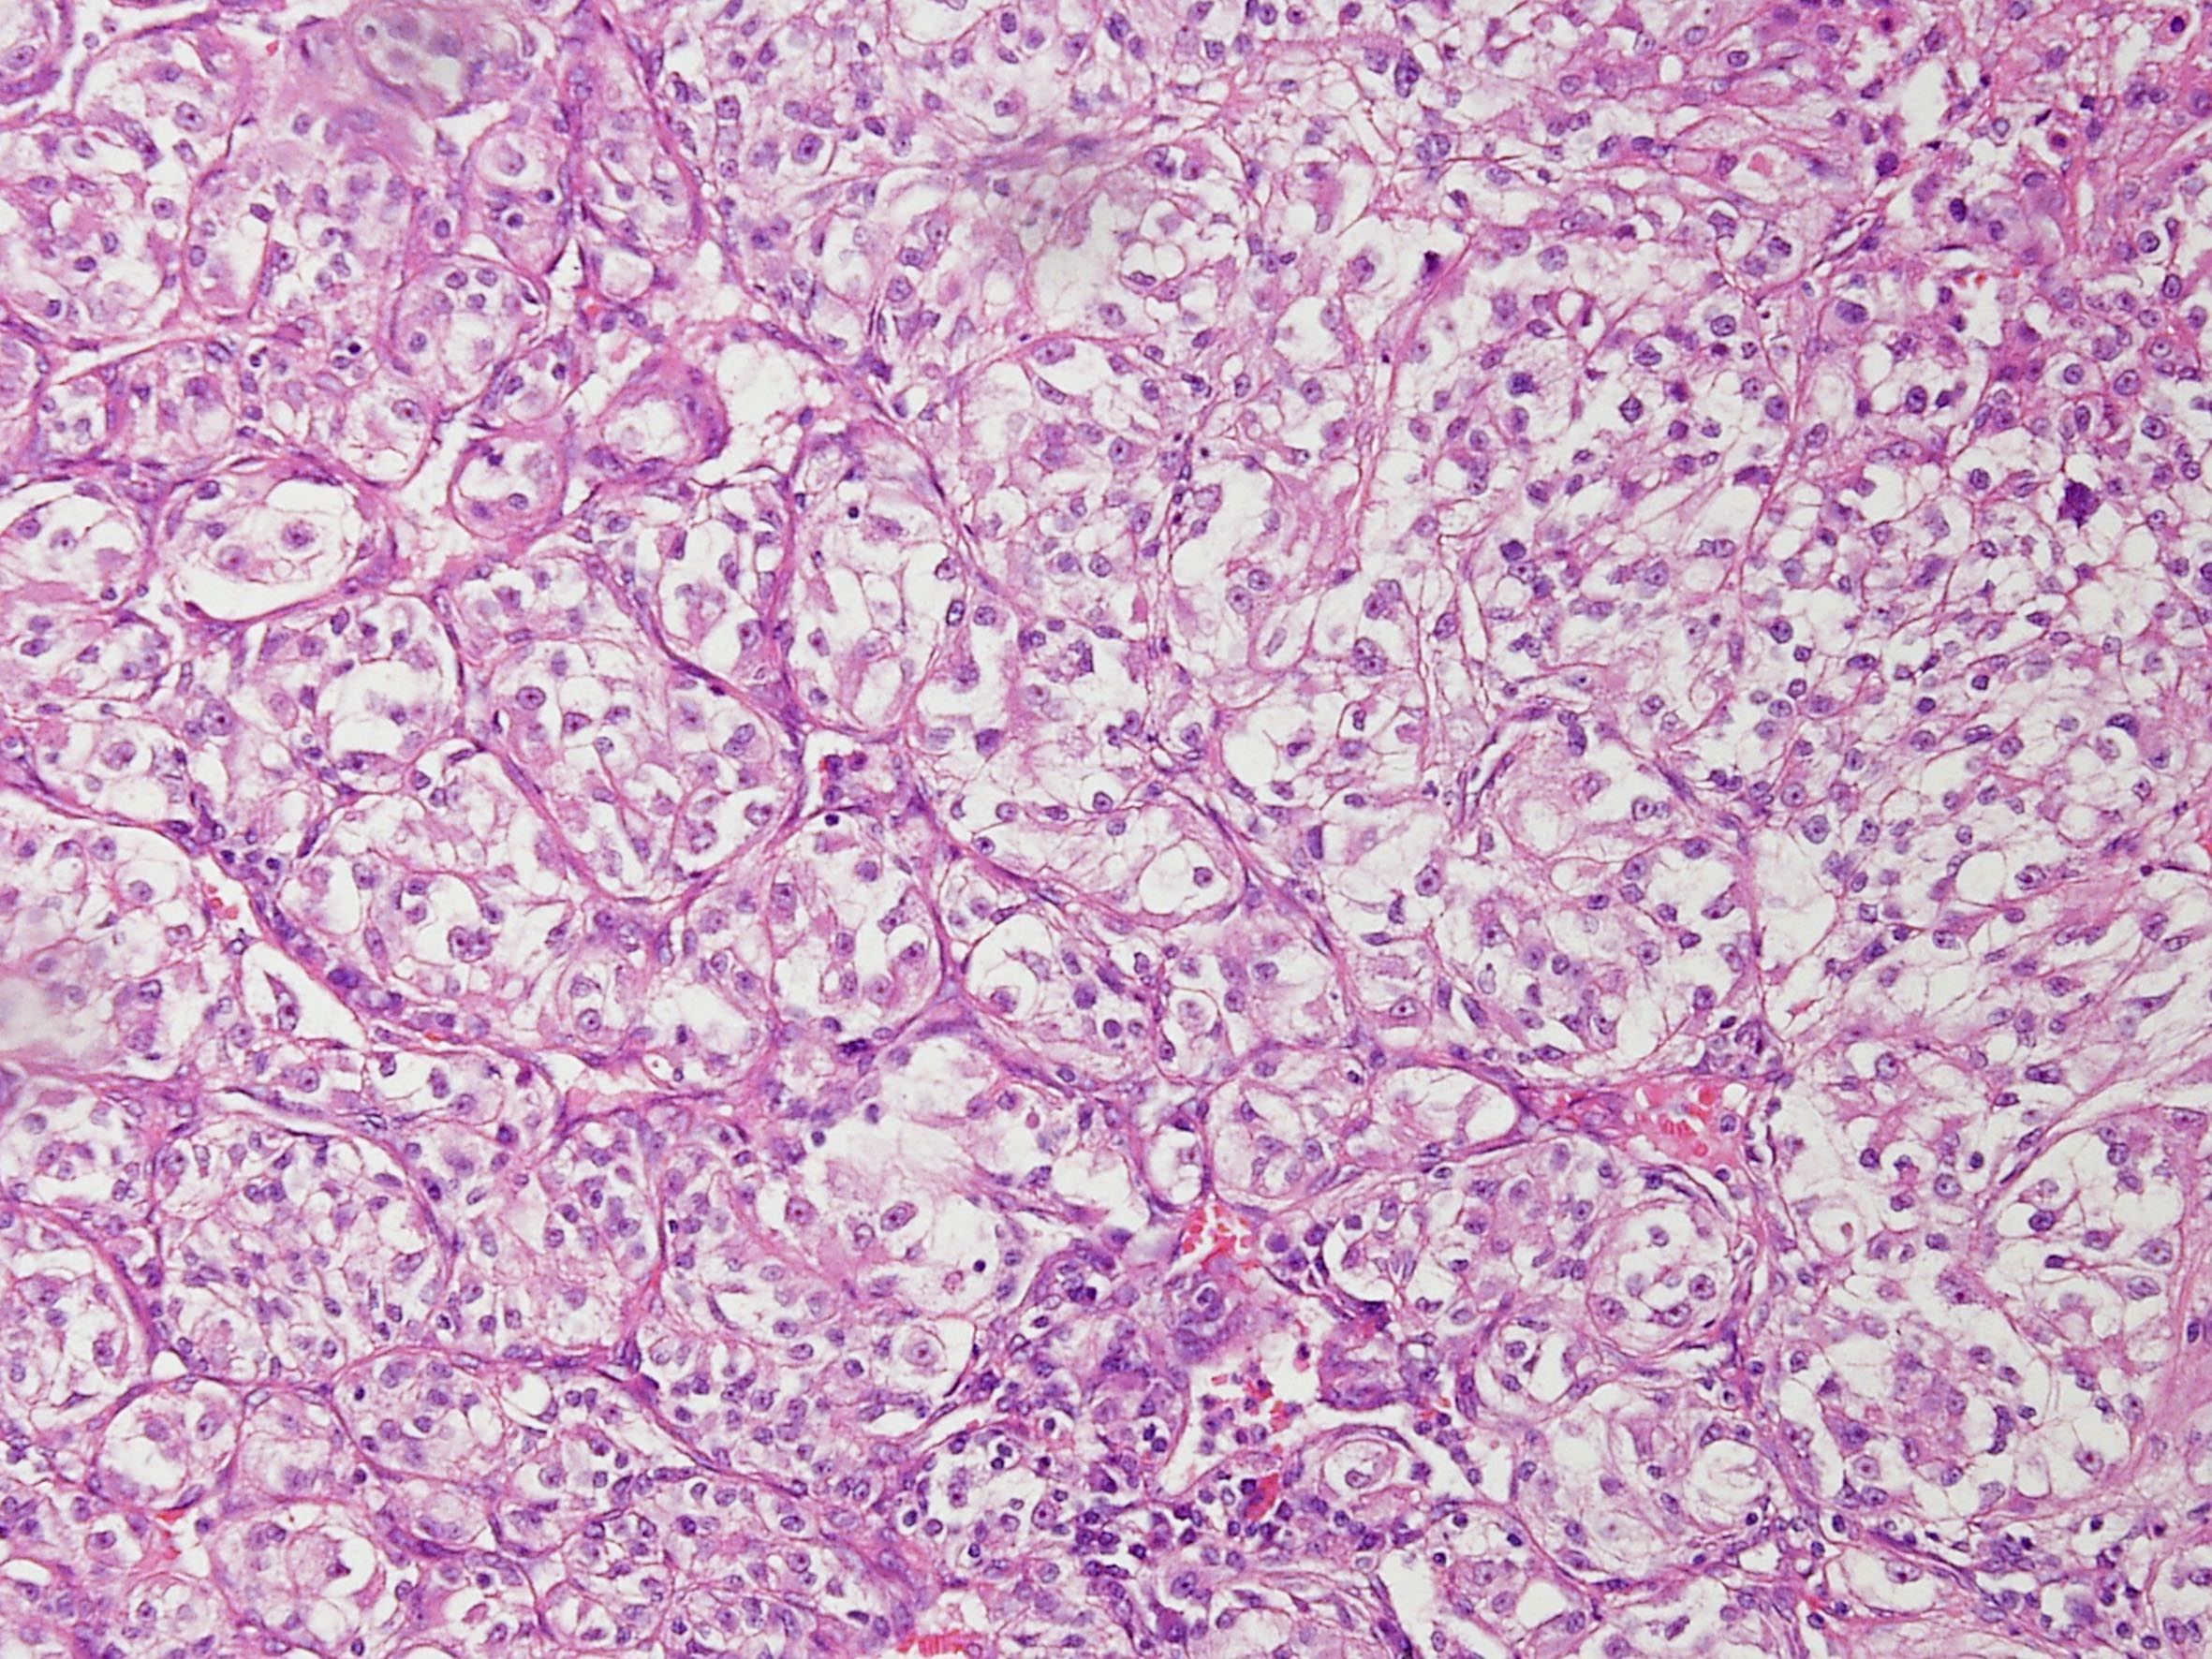

Classification of renal tumors

Case ID: 141